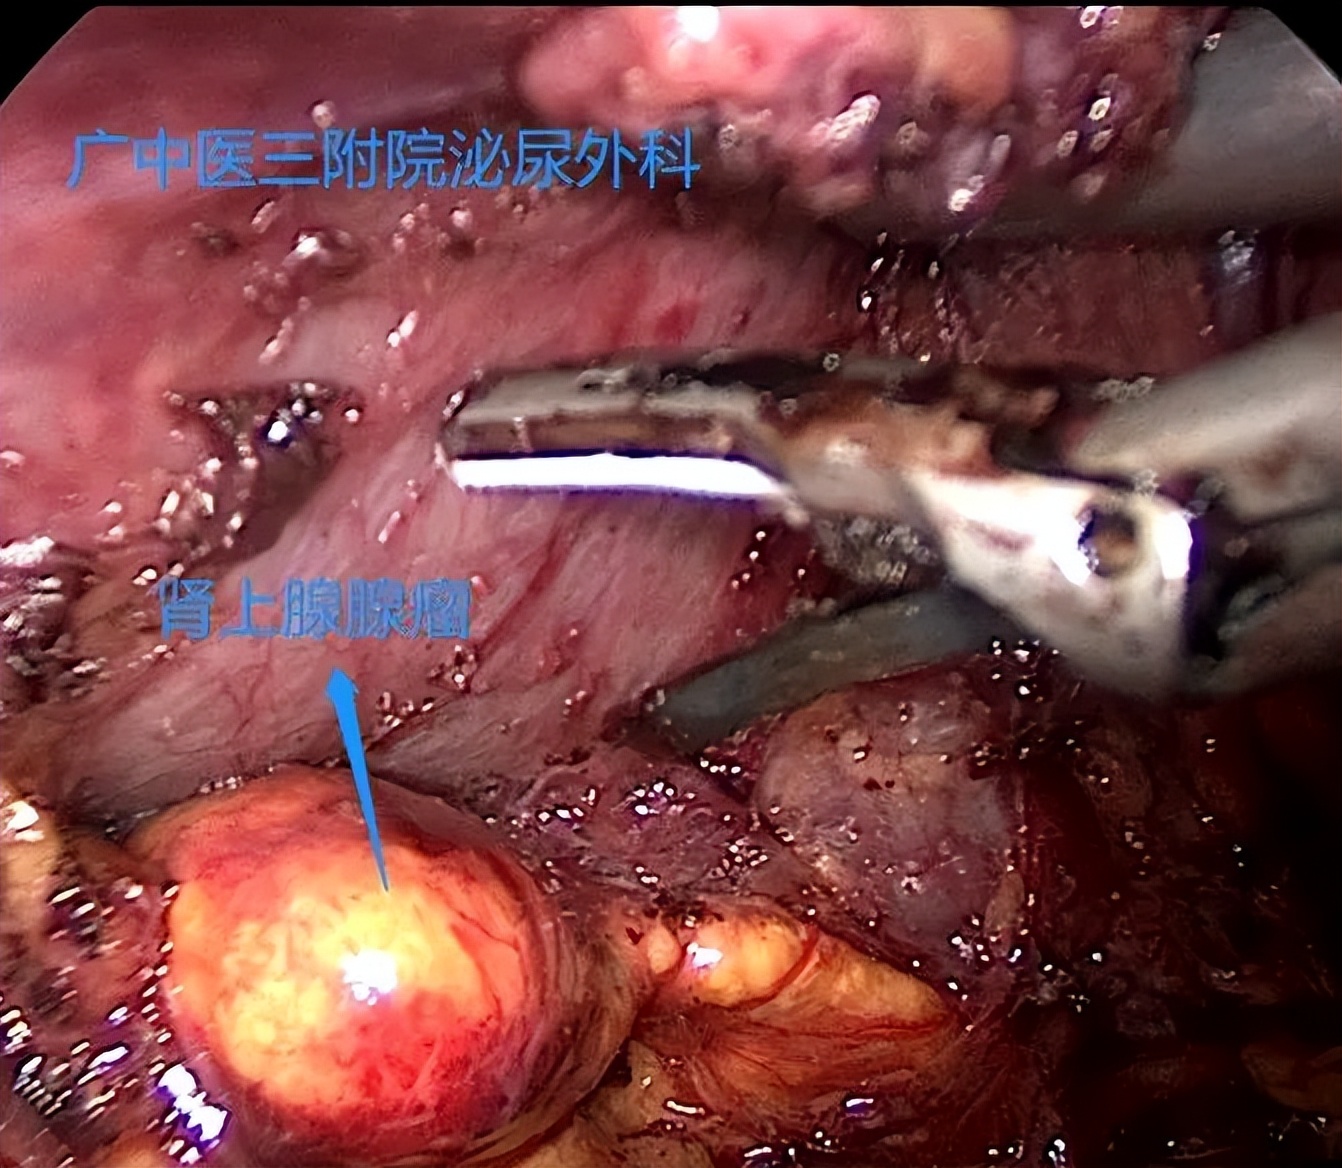

据入院检验检查结果,该患者明确为肾上腺腺瘤导致的原发性醛固酮增多症,引起继发性高血压。为什么肾上腺腺瘤会引发高血压,让我们先了解高血压,

肾上腺病变导致继发性高血压该如何治疗?

外二科副主任医师刘石勇指出,肾上腺腺瘤及肾上腺皮质增生导致的继发性高血压,手术切除是最好的治疗方法。通过手术切除肾上腺病变组织,术后结合降压药物治疗,一般血压可得到较好控制。